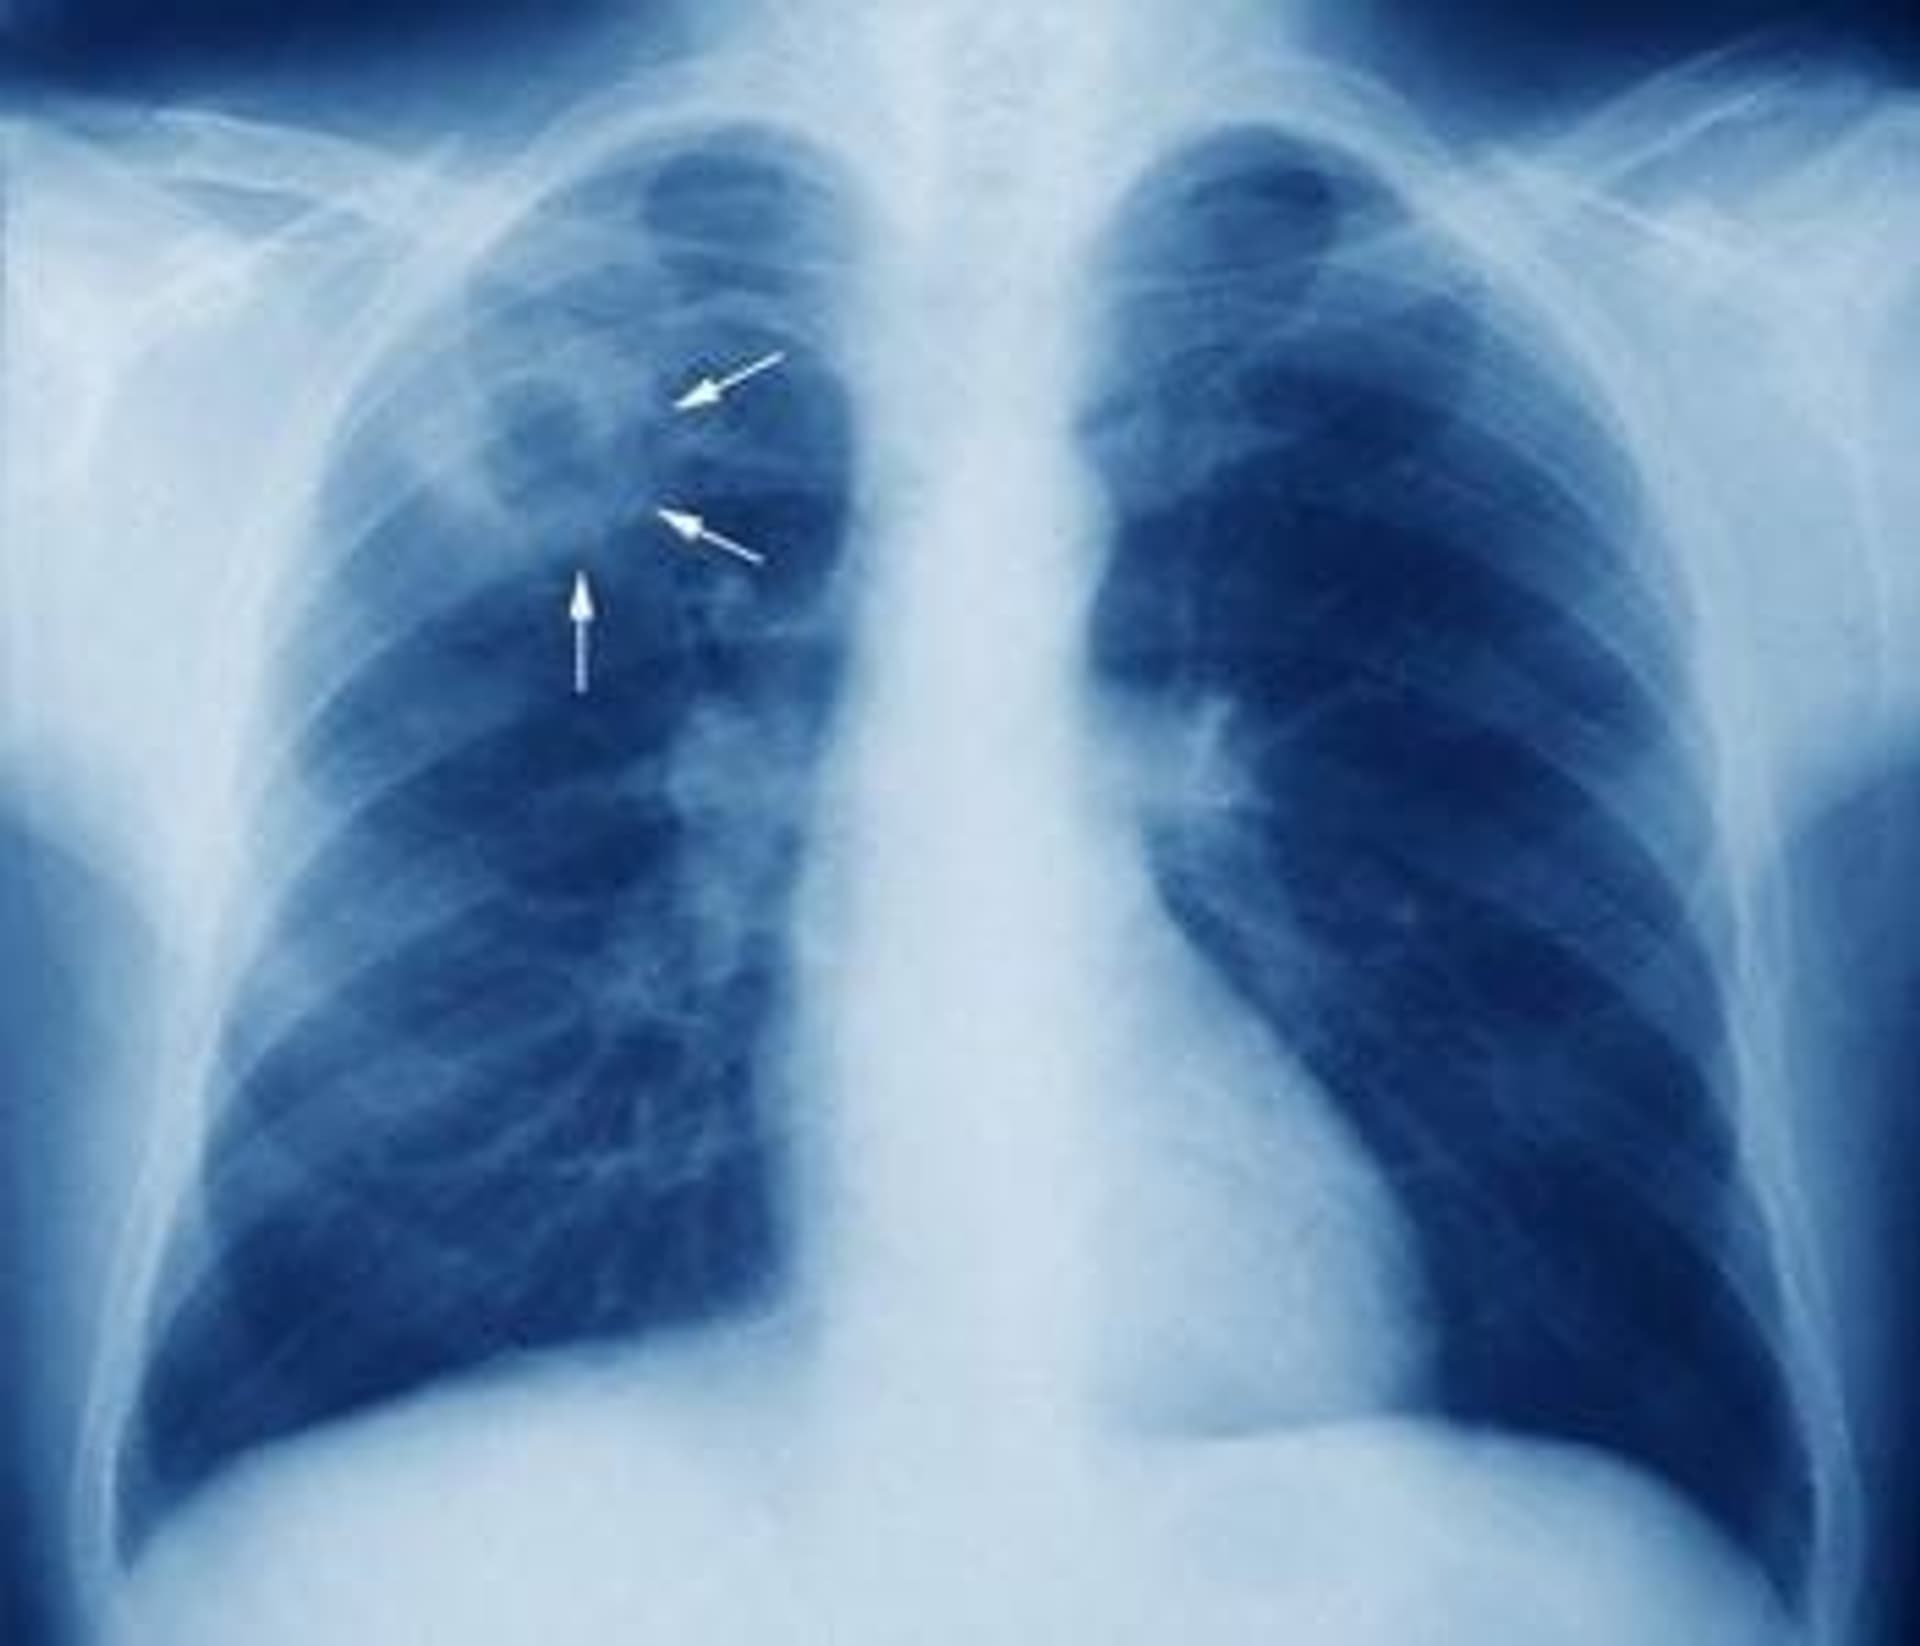

- Vị trí tổn thương: Lao phổi hay bắt đầu từ vùng đỉnh phổi và vùng dưới đòn (phân thùy đỉnh và phân thùy sau của thùy trên phổi). Cơ chế được giải thích là do vi khuẩn lao ái khí và cấu trúc về giải phẫu hệ mạch máu ở đây, làm cho dòng máu chảy chậm so với vùng khác, vì vậy vi khuẩn dễ dừng lại gây bệnh.